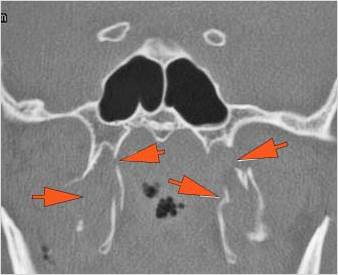

There is evidence of blood products in the paranasal sinuses. [Yes/No]

There is evidence of bony injury along the walls and/or floor of the orbit. [Yes/No]

Orbital blow-out or blow-in fracture [with/without] complications - extent described above.